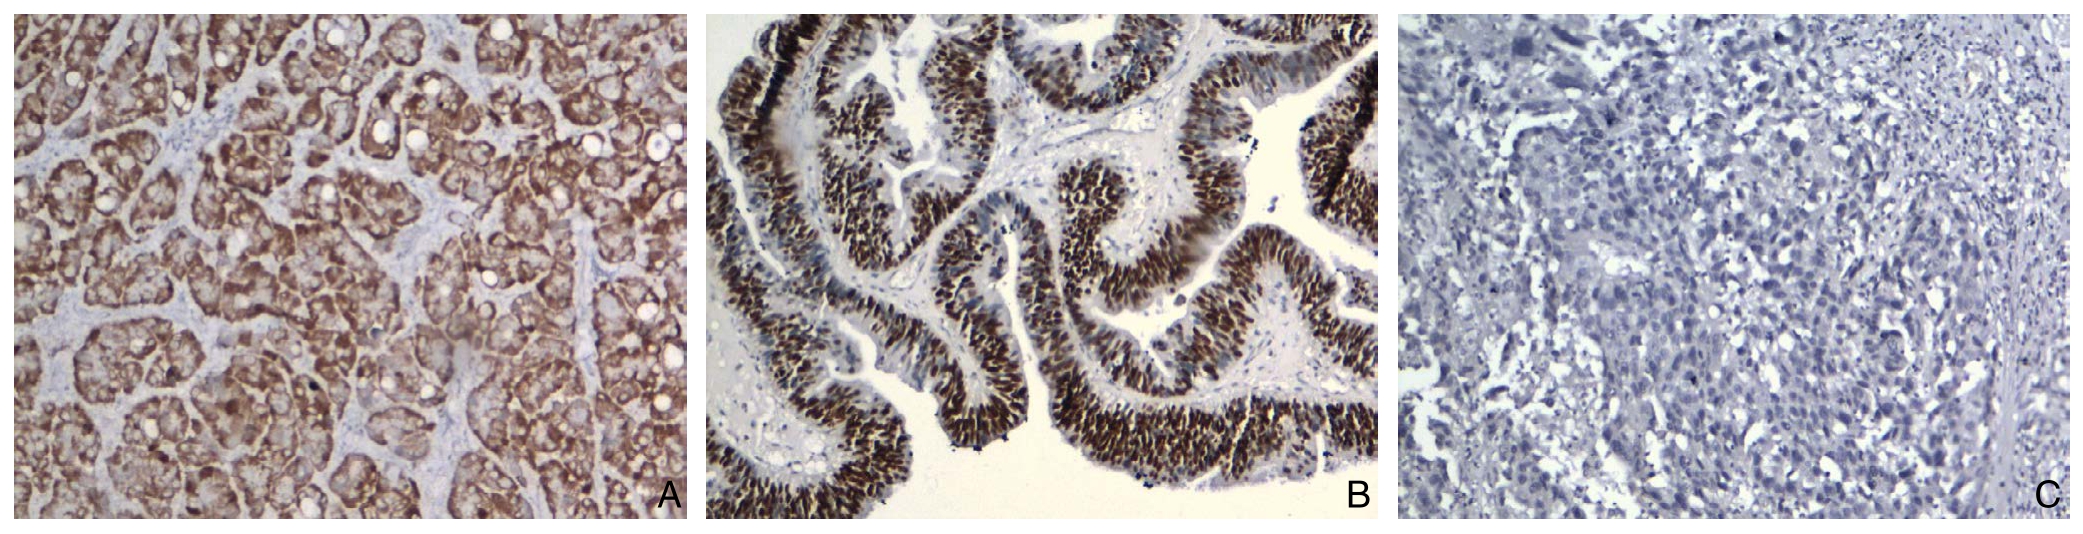

在42例原发性胆管癌组织中Maspin蛋白阳性率为73.8%,42例胆管癌旁组织和12例正常胆管组织Maspin蛋白阳性率分别为21.4%和16.7%,Maspin蛋白阳性率明显高于癌旁组(χ2=23.1,P=0.000)和正常胆管组(χ2=10.5,P=0.01);在42例原发性胆管癌组织p53蛋白阳性率为45.2%,在42例胆管癌旁组织和12例正常胆管组织p53蛋白阳性率均为0,差异均有统计学意义(χ2=22.0,P=0.000;χ2=6.5,P=0.01)(图1)(表1)。

图1 免疫组化检测结果(×100) A:胆管癌组织Maspin阳性表达;B:胆管癌组织p53阳性表达;C:胆管癌组织Maspin阴性表达

Figure 1 Immunohistochemical staining findings A: Positive Maspin expression in cholangiocarinoma tissue; B: Positive p53 expression in cholangiocarinoma tissue; B: Negative Maspin expression in cholangiocarinoma tissue